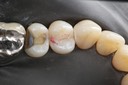

Mark Chun #14 buccal view 2

Mark Chun #14 buccal view